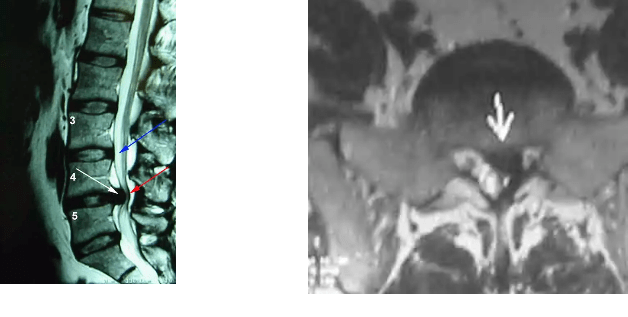

The images below show a white arrow pointing to the disc herniation on the MRI images; The red arrow shows the compression of the nerves in the back [may cause weakness, numbness or bowel and bladder problems]. The disc material is shown [left] when removed which looks like “crab meatâ€.